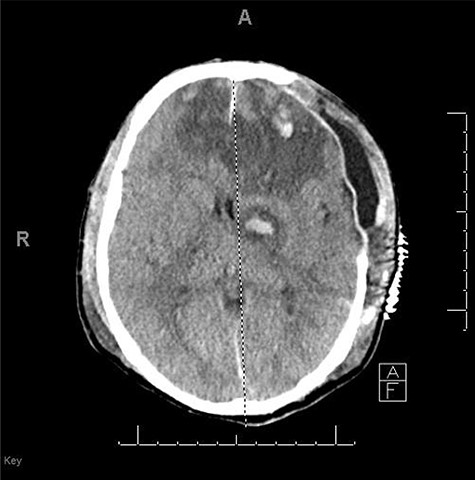

He had a significant recovery, to the point where he was awake with mild right paresis. He was following commands briskly but remained nonverbal. On hospital day 26, he developed neurological deterioration with decreased mental status and worsening right hemiparesis. Clinical examination noted pronounced new indentation of his hemicraniectomy flap site. CT head showed a rightward shift away from the craniectomy site and impending herniation (Fig. 4).

CT head POD26 from craniectomy demonstrating findings consistent with SSFS.